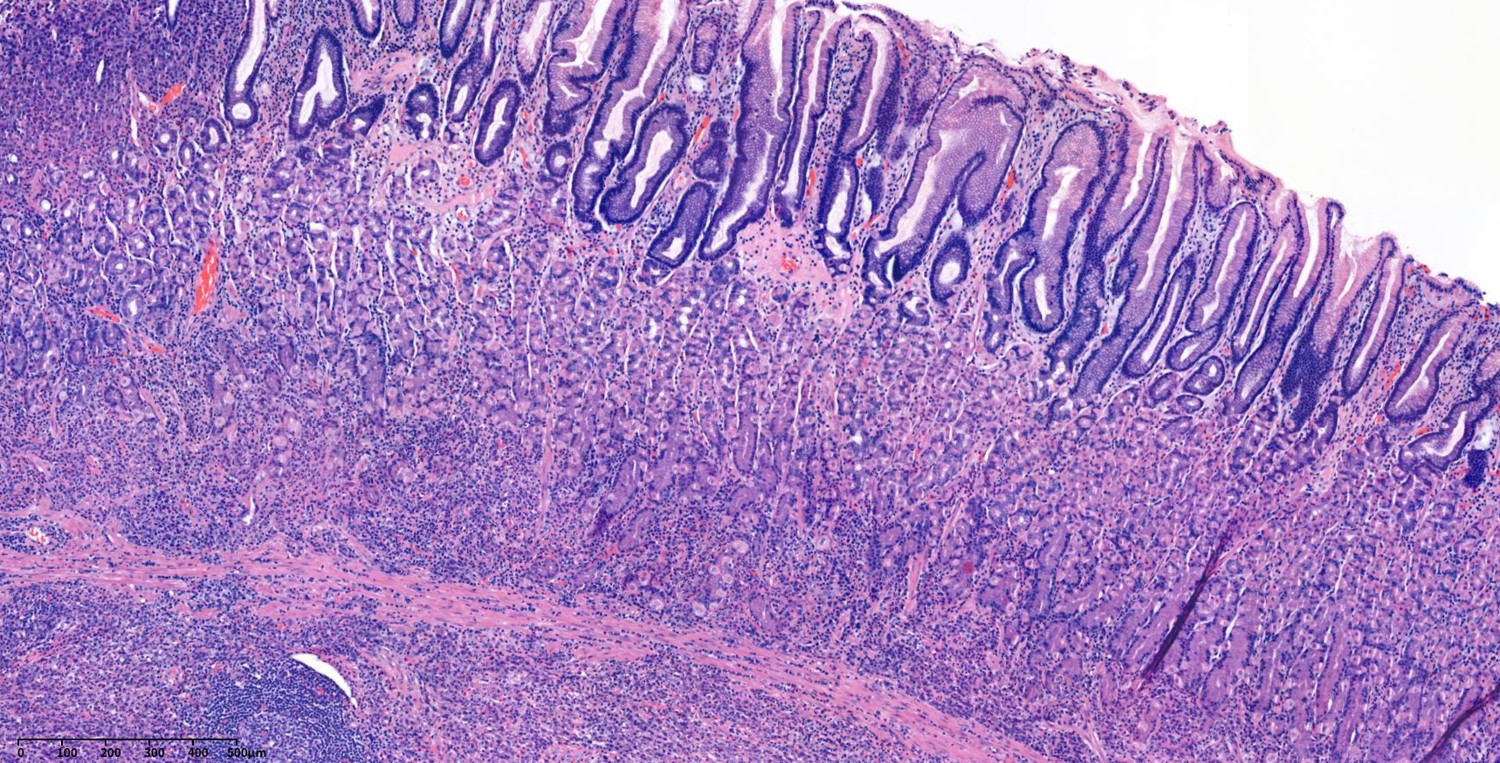

This is a typical case with AGC with serosal invasion.

Serosal invasion is T4a.